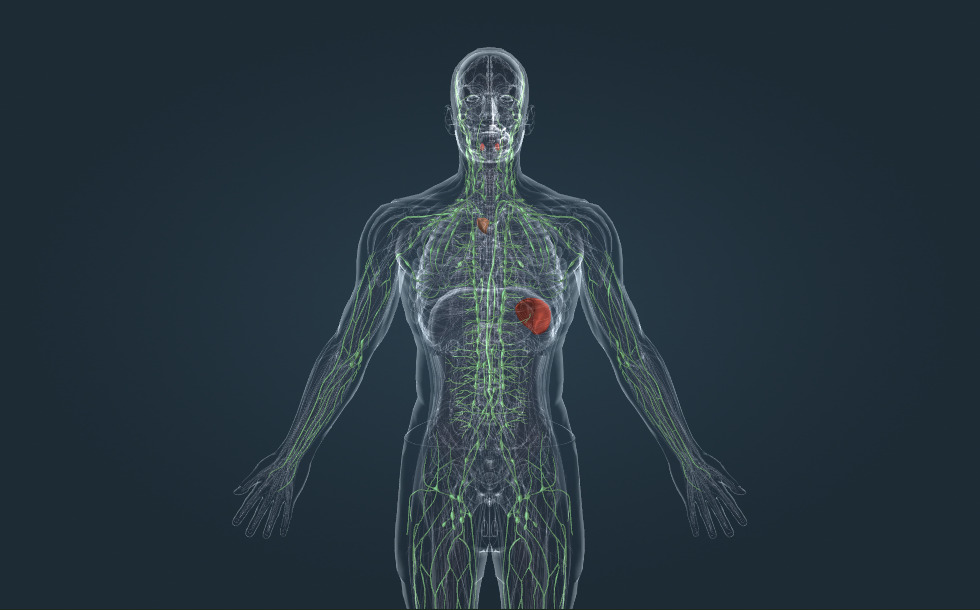

Sistema linfático

- amígdala

- bazo - Tiene un importante papel en la maduración de los leucocitos y en el funcionamiento del sistema inmunitario.

- timo - Tiene un importante papel en la maduración de los leucocitos y en el funcionamiento del sistema inmunitario.

- ganglio - Tiene un importante papel en la maduración de los leucocitos y en el funcionamiento del sistema inmunitario.

- conducto torácico - El conducto torácico drena en la vena subclavia izquierda donde la linfa se mezcla con la sangre y llega al corazón.

- vaso linfático

La linfa es el fluido en los espacios intersticiales, también conocidos como los espacios de los tejidos. Se produce a partir de la sangre por ósmosis a través de las paredes de los capilares. Los productos del metabolismo también llegan a la linfa. La linfa se transporta a la vena subclavia por los vasos linfáticos y también pasa por los ganglios. Los patógenos transportados por la linfa se reúnen con las células sanguíneas blancas que viven en los ganglios linfáticos, de gran importancia para el funcionamiento del sistema inmunitario. Otros órganos linfáticos importantes incluyen el timo, el bazo y las amígdalas: además, desempeñan un papel importante en la maduración de las células blancas de la sangre y en la defensa inmunitaria.

La linfa es el fluido en los espacios intersticiales, también conocidos como los espacios de los tejidos. Se produce a partir de la sangre por ósmosis a través de las paredes de los capilares. Los productos del metabolismo también llegan a la linfa. La linfa se transporta a la vena subclavia por los vasos linfáticos y también pasa por los ganglios. Los patógenos transportados por la linfa se reúnen con las células sanguíneas blancas que viven en los ganglios linfáticos, de gran importancia para el funcionamiento del sistema inmunitario. Los órganos linfáticos importantes incluyen el timo, el bazo y las amígdalas: además, desempeñan un papel importante en la maduración de las células blancas de la sangre y en la defensa inmunitaria.